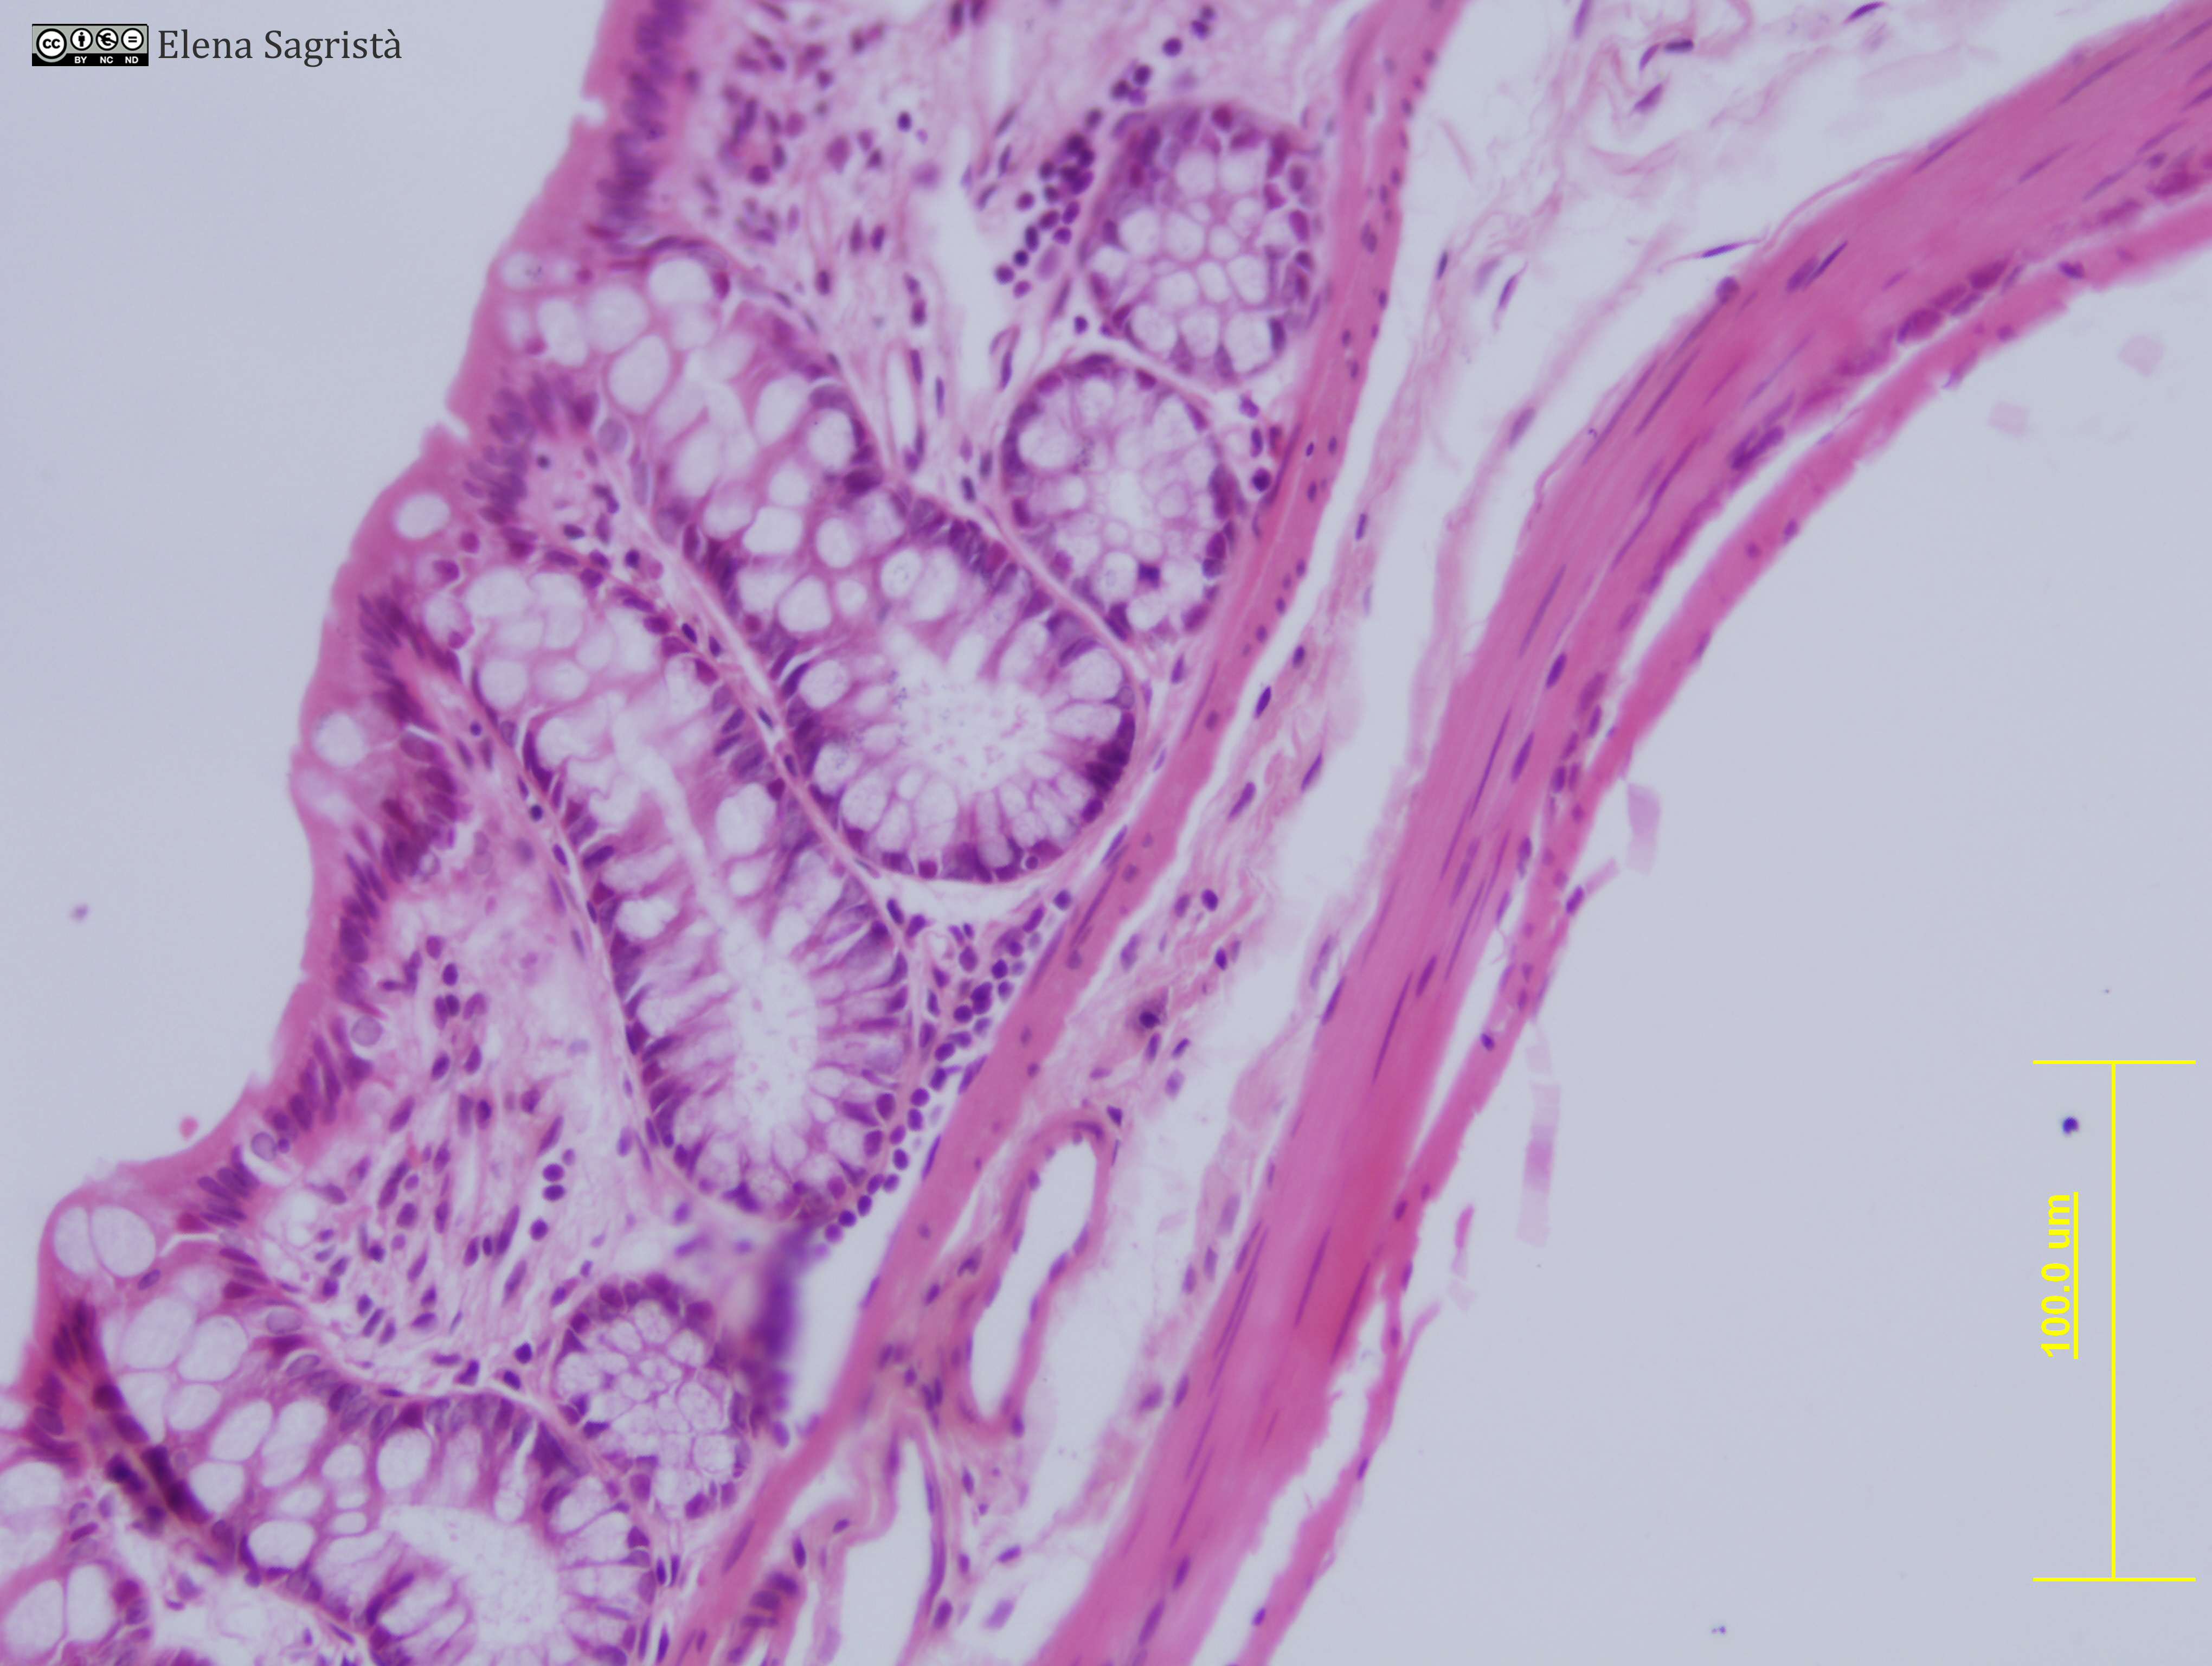

Histologia imatges: 18 Intestí gros

Imatges de preparacions histològiques d'Intestí gros. Microscopia òptica.